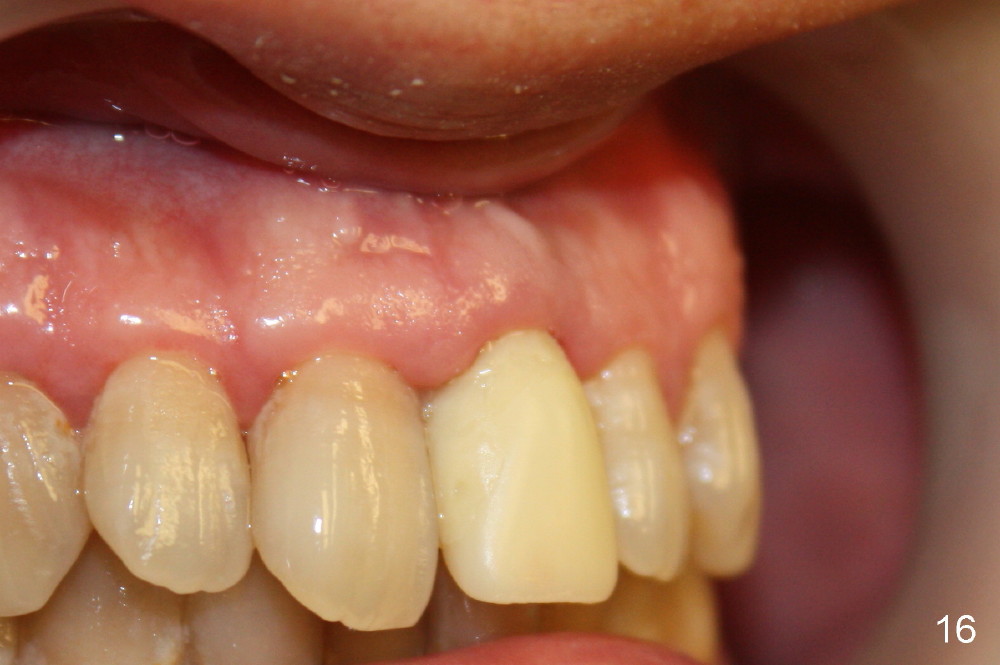

Bone expansion allows the implant (Fig.9 I) to have primary stability (insertion torque between 50 and 60 Ncm), since the cortex of the incisive canal is apparently intact.  Allograft is placed in the labial gap (Fig.10, 11 *) following installation of the abutment (A).  Finally an immediate provisional (Fig.10,12 P) is cemented.  Fig.13,14 are taken 8 days postop.  The patient returns 3 months postop (Fig.15,16).  Osteointegration appears to have occurred (Fig.15 arrowheads) and is more obvious 9 months postop (Fig.17).

The permanent crown is temporarily cemented because of misshade and undercountour at the cervix (Fig.18).